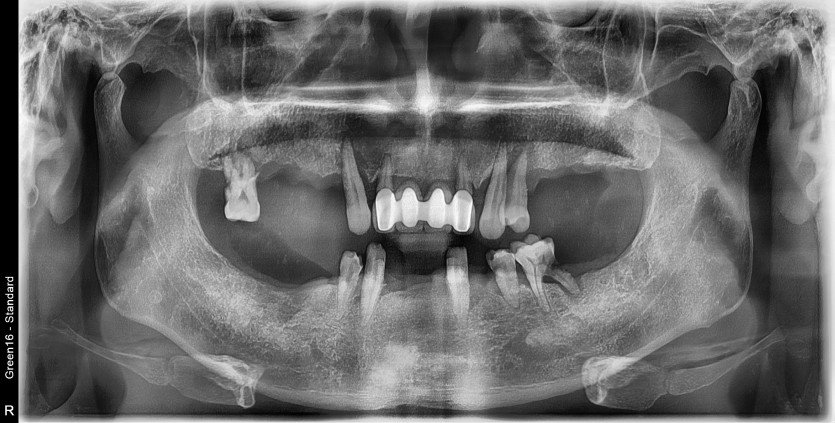

전체 임플란트 증례입니다.

18개의 임플란트로 완성하였습니다.